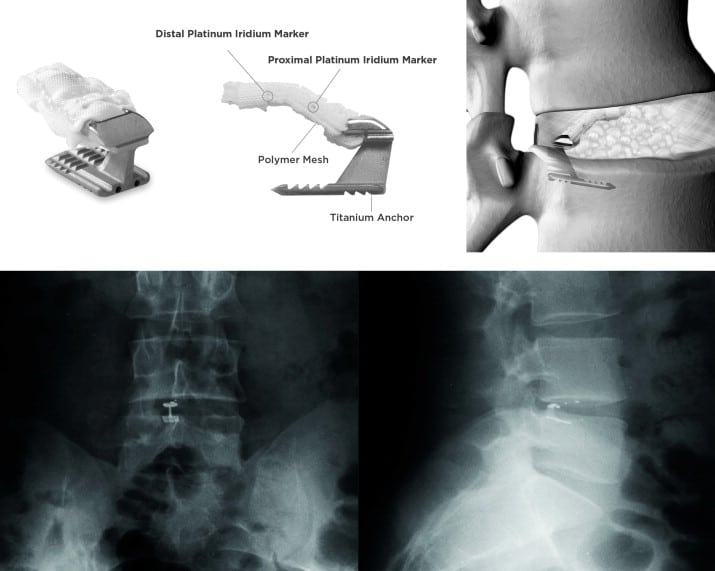

Barricaid surgery is a minimally invasive procedure used to treat back pain caused by disc herniation or degeneration. The Barricaid implant is placed into the damaged disc, providing support and preventing further disc material from pressing on the nerves. This helps reduce pain and restore function in the spine. The surgery is often recommended for patients who haven’t found relief from traditional treatments such as physical therapy or medication.